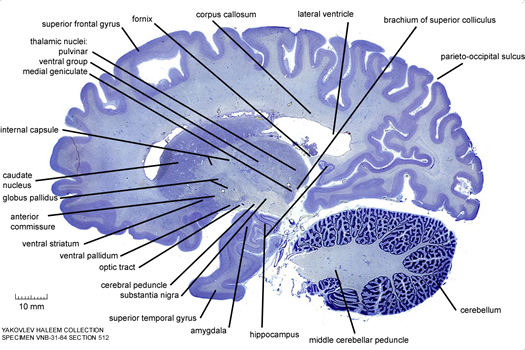

| Cerveau |

Centre de coordination du système nerveux, le cerveau est chez l'Homme constitué de 1000 milliards de cellules, dont 100 milliards de neurones. Il est entouré par des tissus protecteurs, les méninges, et protégé par la boîte crânienne.

Le cerveau comprend notamment deux hémisphèrescérébraux, droit et gauche. Leur surface externe, le cortex, est constituée de susbtance grise, plissée en de nombreuses circonvolutions cérébrales.

On distingue cinq lobes dans les hémisphères cérébraux : frontal, pariétal, temporal, occipital et insulaire (caché au fond de la "vallée sylvienne".

| Cortex cérébral |

Partie superficielle du cerveau formé par de la substance grise. On distingue six couches de neurones superposées, qui forment différentes aires spécialisées dans des fonctions bien précises. Le cortex cérébral mesure 5 mm d'épaisseur et développe une surface de 2000-2500 cm2 (grâce aux nombreuses circonvolutions cérébrales). Il contient 100 milliards de neurones.

| Cortex pariétal |

Cortex du lobe pariétal.

| Gyrus |

Pli convexe du cortex cérébral. Exemple : gyrus supra-marginal localisé.......

Hémisphère cérébral

|

Le Cerveau comprend notamment deux hémisphères cérébraux, droit et gauche. Leur surface externe, le cortex, est constituée de susbtance grise, plissée en de nombreuses circonvolutions cérébrales.

On distingue cinq lobes dans les hémisphères cérébraux : frontal, pariétal, temporal, occipital et insulaire (caché au fond de la "vallée sylvienne".